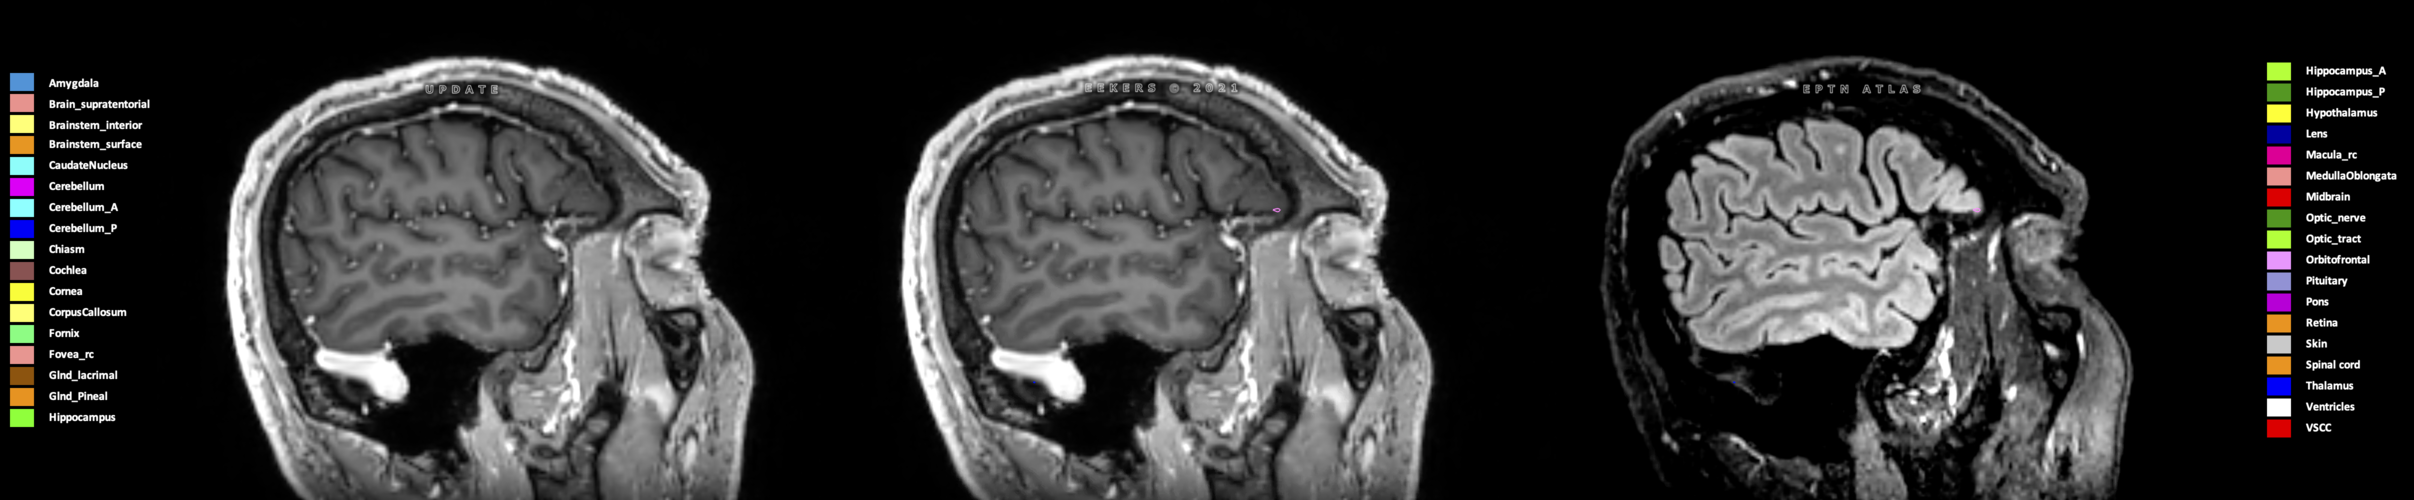

Eekers et al. have published an international neurological atlas for contouring of organs at risk in consensus with the European Particle Therapy Network (EPTN) in 2018 and an update in 2021. The purpose of this consensus atlas is to decrease inter- and intra-observer variability in delineating OARs relevant for neuro-oncology.

Included are all OARs known to be relevant for radiation-induced toxicity in neuro-oncology: brain, brainstem (midbrain, pons, medulla oblongata), chiasm, cerebellum (anterior & posterior), cochlea, cornea, hippocampus (anterior & posterior), hypothalamus, lens, lacrimal gland, optic nerve, pituitary, skin, and vestibular & semicircular canals. To further facilitate research on cognition, vision and radiological changes after irradiation of the brain, potential clinically-relevant OARs are included: amygdala, caudate nucleus, cerebellum (anterior & posterior), corpus callosum, fornix, macula, optic tract, orbitofrontal cortex, periventricular space (PVS), pineal gland, and thalamus.

We propose this atlas is used in photon and particle therapy in order to derive consistent dosimetric data. When required this atlas will be updated according to new insights.

Three-dimensional delineation of the 25 consensus OARs for neuro-oncology are shown on CT (WW/WL 120/40, 3000/600), 3T MR images, (T1Gd, T2FLAIR 1mm) and 7T MR (MP2RAGE 0.7 mm). All are presented in transversal, sagittal and coronal view.